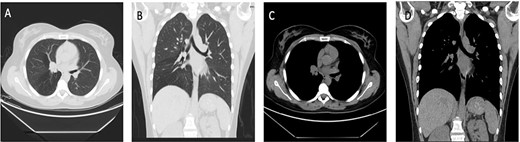

The second case involved a 46-year-old male, who was a smoker for 15 years, however, had quit smoking for 1 year prior to presentation, otherwise medically and surgically free. He had a main complaint of periodic hemoptysis. This patient’s CT scan (Fig. 2) showed a 2.2 × 2 cm lesion at the level of the carina. Operatively, the lesion was resected en bloc in a similar fashion to the first portrayed case, using a combination of bronchoscopic snare and electrocautery. Pathology revealed an endotracheal typical carcinoid tumor (Fig. 1; case 2).

Case 2: panels (A and B) show an intratracheal soft tissue mass just above the carina more toward the left side. (C and D) Same lesion on axial cuts with radiological evidence of infiltration/invading left lateral wall of the trachea.